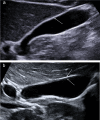

Gallbladder polyps are protuberances of the gallbladder wall projecting into the lumen. They are usually incidentally found during abdominal sonography or diagnosed on histopathology of a surgery specimen, with an estimated prevalence of up to 9.5% of patients. Gallbladder polyps are not mobile and do not demonstrate posterior acoustic shadowing; they may be sessile or pedunculated. Gallbladder polyps may be divided into pseudopolyps and true polyps. Pseudopolyps are benign and include cholesterolosis, cholesterinic polyps, inflammatory polyps, and localised adenomyomatosis. True gallbladder polyps can be benign or malignant. Benign polyps are most commonly adenomas, while malignant polyps are adenocarcinomas and metastases. There are also rare types of benign and malignant true gallbladder polyps, including mesenchymal tumours and lymphomas. Ultrasound is the first-choice imaging method for the diagnosis of gallbladder polyps, representing an indispensable tool for ensuring appropriate management. It enables limitation of secondary level investigations and avoidance of unnecessary cholecystectomies.